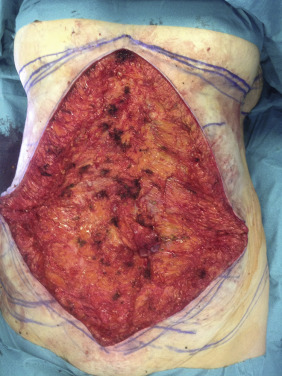

Vertical Resection ( Fig. 32.3 )

The extent of the vertical resection is best marked with the patient in the supine position on the operating table. The maximum resection is marked on each side by pinching the flank skin into the midline. The skin is tailor-tacked with staples in the correct position. A vertical line is drawn from the IMF to the pubis on each side of the staple line. When the staples are removed, the amount of skin resection can be seen. There should be the same amount of skin resection on each side, which can be checked with a ruler.

The skin markings are incised with a No. 10 blade, and dissection is commenced vertically down to the rectus fascia using the hand-held diathermy. The umbilicus is circumscribed and dissected free from the abdominal flap. The vertical skin flap is resected off the abdominal wall. Hemostasis is secured.